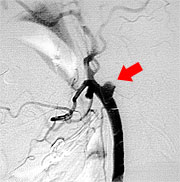

すでに詰まってしまっている患者さんに対しては症状が軽い場合であれば、頭蓋内血管と頭蓋外血管とのバイパス手術を行い、症状の悪化を予防しています(図11,図12,図13)。